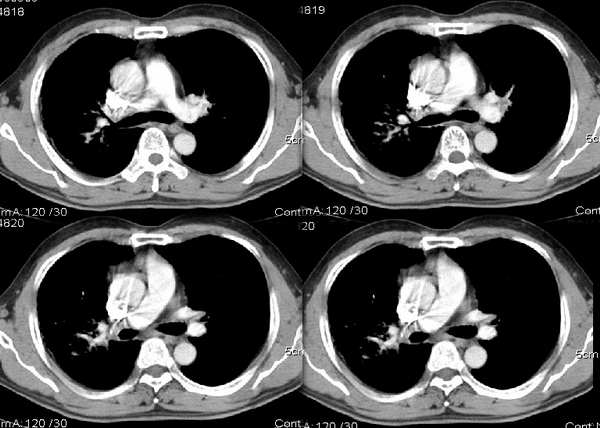

男54岁咳嗽咯痰2w,外院胸片示“右上大叶性肺炎抗炎治疗后部分吸收

请问右中叶支气管开口旁不强化结节影是什么?

右上叶支气管变窄.ca?